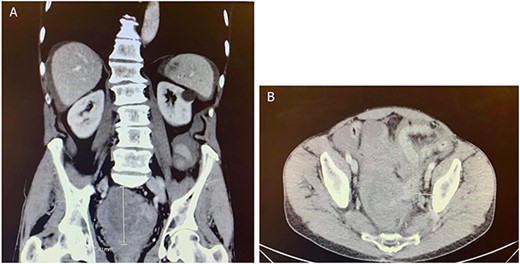

Computed tomography (CT) of the abdomen and pelvis showed moderate-to-large volume hemoperitoneum. The epicenter of the hemorrhage appeared to be in the pelvis where a rectovesical hematoma mass measured 8.2 × 7.0 cm (Fig. 1). The center of the hematoma raised suspicion for active hemorrhage consistent with contrast blush. No source of bleeding was identified on arteriography. Magnetic resonance imaging (MRI) with contrast ensued and suggested small bowel segment involvement in the lateral side wall of the hematoma within the pelvis (Fig. 2). Considering the patient presentation, imaging, and declining hemoglobin (Hb 8.3 g/dl), the patient was brought to the operating room for an exploratory laparotomy. Old blood was immediately encountered upon entering the abdomen during surgery. An exophytic mass, about 5 cm in diameter located on the antimesenteric border of the mid jejunum, was noted. The mass was actively oozing and was determined to be responsible for the hemoperitoneum. Specimens from the pelvic side wall, small bowel, and the hematoma were collected and sent to pathology. Small bowel resection with anastomosis was performed on the main tumor, though it was thought that residual disease was left. All segment pathology diagnoses showed over 5 cm with 11 mitoses per 5 mm2 GIST with associated blood clot, confirming stage 4 disease.

CT abdomen and pelvis with contrast in (A) anterior–posterior and (B) coronal views identified a rectovesical hematoma mass measuring 8.2 × 7 cm.